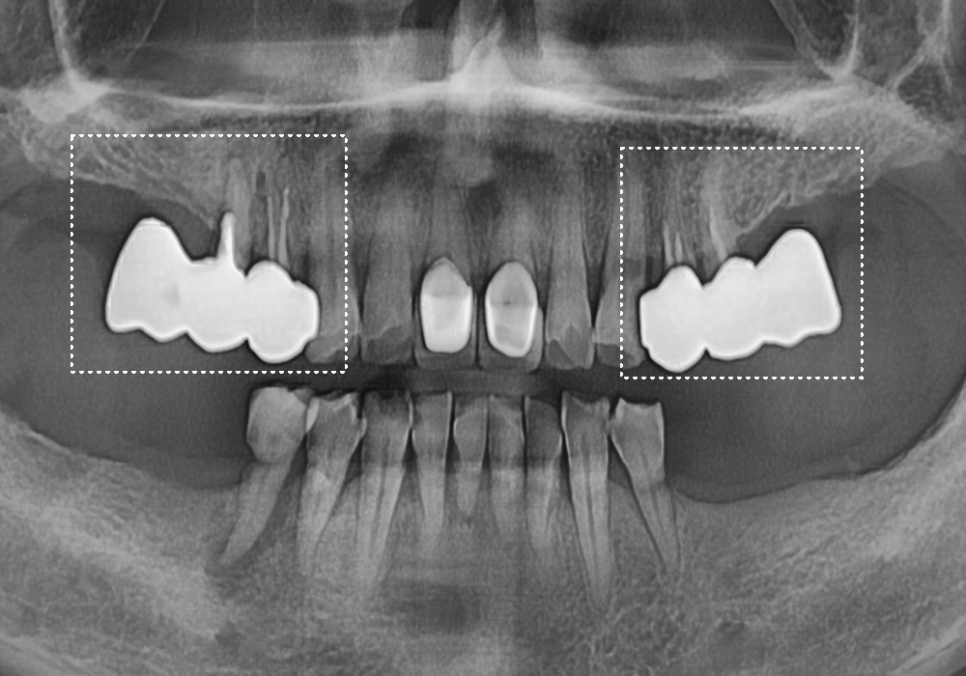

이 환자분은 아래 앞니가 흔들려

저희 병원에 내원하셨습니다.

방사선 진단 결과,

치조골(뼈)이 전반적으로

많이 흡수되어 있었고,

그로 인해 치아 뿌리를

지지하는 힘이 부족해

치아가 흔들리는 상태였습니다.

또한 뼈가 지지해 주는

치근(뿌리) 길이도 매우 짧아

자연치로 유지하기에는

예후가 좋지 않은 상황으로

판단되었습니다.